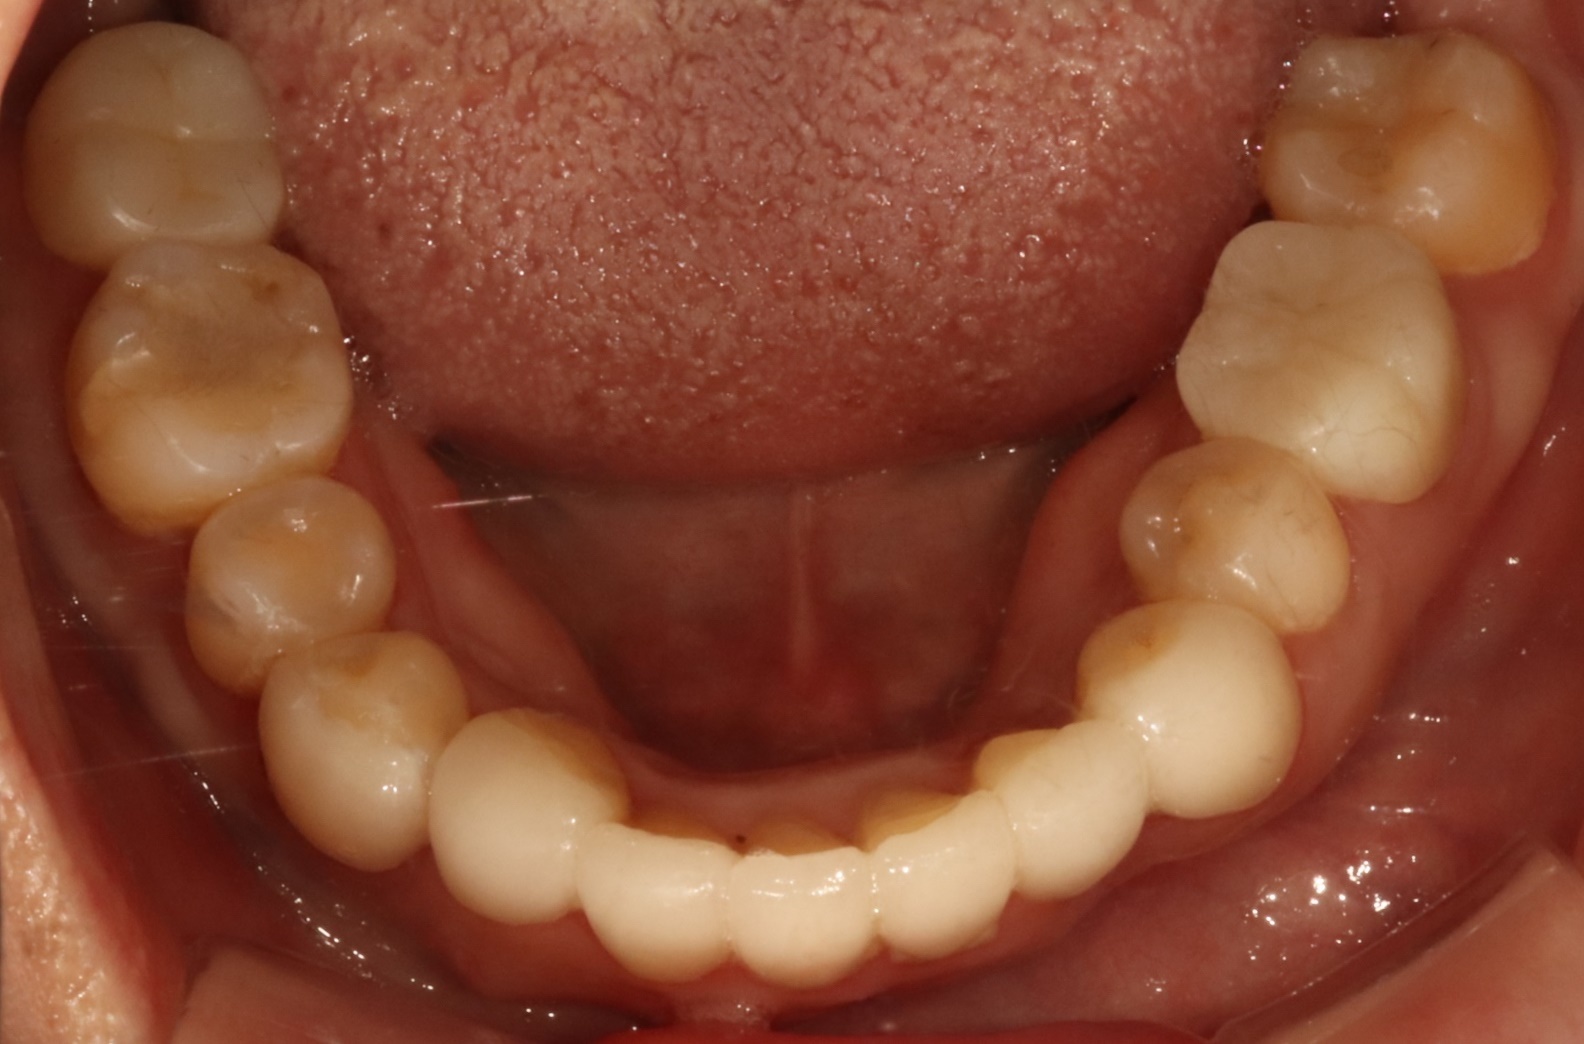

어금니 크라운

Before

After

대량 충치로 손상된 어금니 완전 복원